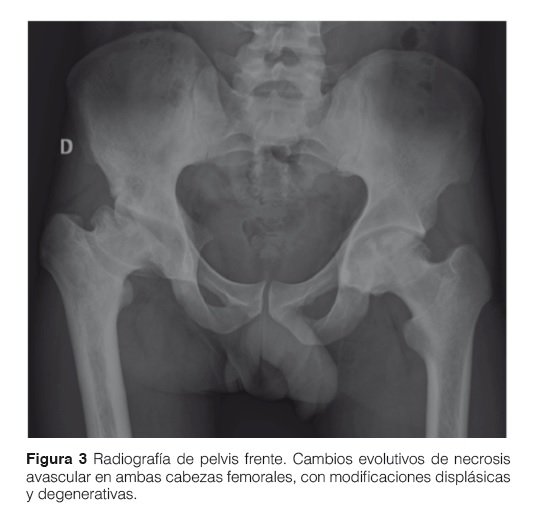

La Radiología muestra la forma y estructura del hueso además de sus relaciones articulares. Es un método simple, rápido y de fácil acceso. El hueso se afecta de manera secundaria a la afectación de la medula ósea. Por eso los cambios son tardíos. Sin embargo nos permite saber de manera rápida la historia de la enfermedad y la gravedad del compromiso óseo, evaluar la presencia de fracturas, infartos, necrosis vascular, compromiso articular y grado de remodelación ósea. Secundariamente y de manera menos precisa también podemos evaluar la densidad mineral ósea (Fig. 2 y 3).

Las lesiones óseas en la EG se clasifican en reversibles a la terapia de reemplazo enzimático (TRE) como la infiltración medular y la alteración en frasco de Erlenmeyer especialmente en la edad pediátrica y lesiones óseas irreversibles a la TRE: necrosis ósea avascular e infarto medular. La deformación en matraz de Erlenmeyer en un paciente en edad adulta debe ser considerada como lesión ósea irreversible (Fig. 6).